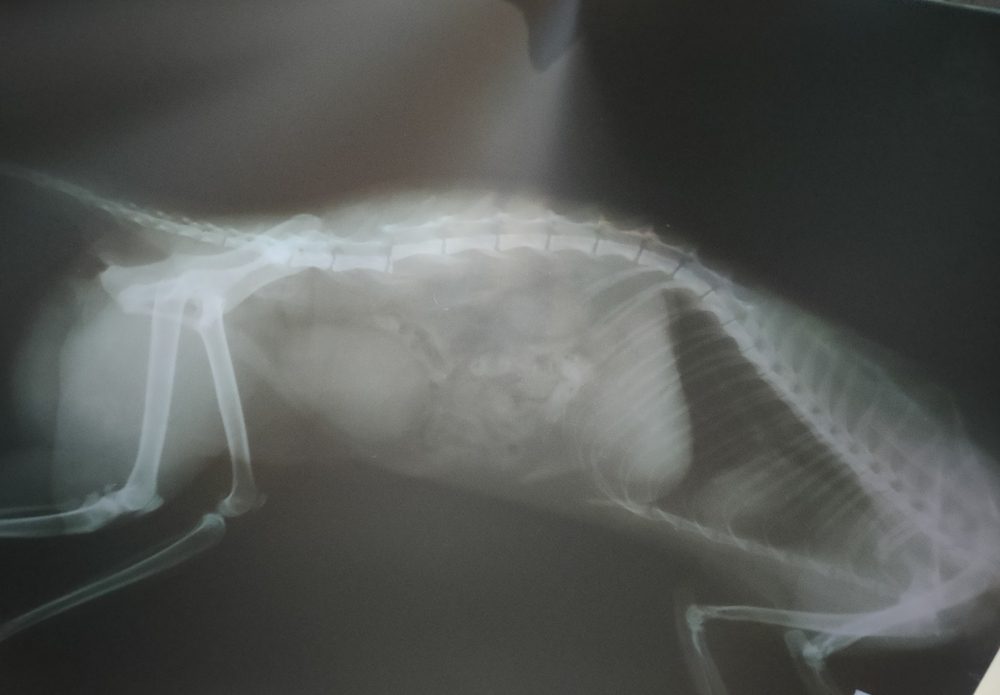

X-rays (Radiography):

Principle: X-rays pass through tissues and are absorbed differently based on density. Dense structures (like bones) appear white, while softer tissues appear gray.

Emergency: Assess fractures, dislocations, and foreign bodies.

Non-Emergency: Evaluate joint degeneration, lung conditions, and dental issues.